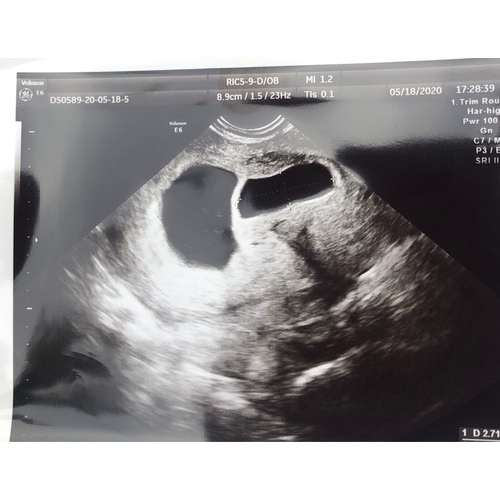

Afgelopen weken af en toe bruine spotting gehad, toen een week niet. Afgelopen vrijdag (7,5 week) opeens heel veel bruin verlies. Ik mocht gelijk langskomen voor een echo. Een heel mooi hartje zien kloppen.